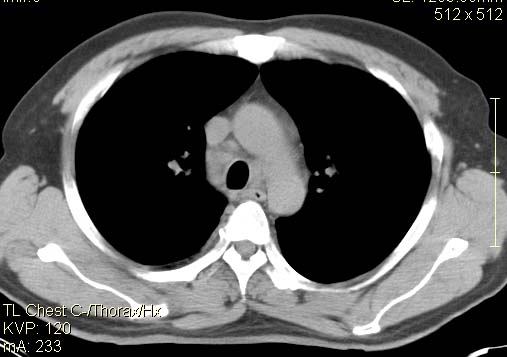

以下是引用qc80012345在2007-4-17 12:33:00的发言:[br]右肺下叶周围型肺癌伴肺门及纵隔内淋巴结转移;比较清楚。

以下是引用qingyuan在2007-4-17 14:19:00的发言:[br]右肺下叶外侧后段胸膜下区节结样病变、分叶、内可见空洞,壁厚薄不均,胸膜凹陷、肺门周围区纹理增粗、僵硬、并近似小结节样改变,肺门区软组织节结、纵膈淋巴结肿大,患者病史长、抗炎治疗无好转炎性改变基本排除,考虑:右肺下叶周围型肺癌伴纵膈及右肺门区淋巴结转移、肺内淋巴管受侵。